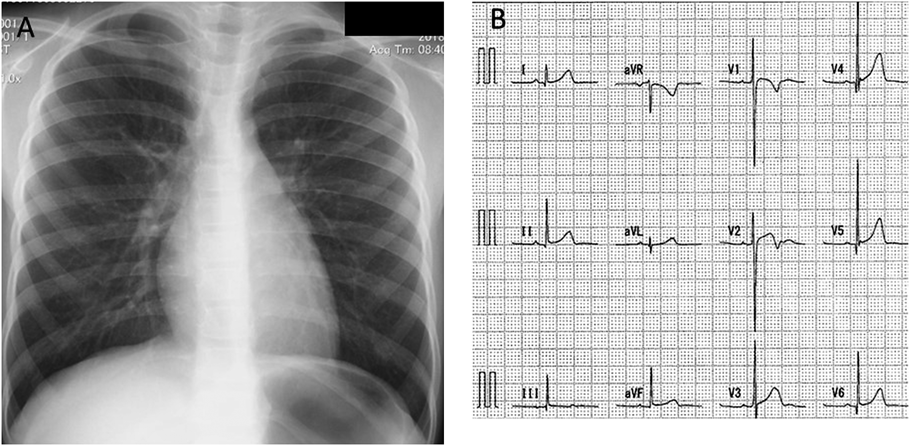

Chest radiograph showed a cardiothoracic ratio of 42%, and a 12-lead electrocardiogram at rest was normal with no ST changes (Fig. 1). Blood tests showed no abnormal findings with a human brain natriuretic peptide (BNP) level of 13.0 pg/mL. Echocardiography findings are shown in Fig. 2. The left ventricular end diastolic diameter was 30.1 mm (84.3% of our normal value), end systole diameter was 19.5 mm with ejection fraction of 70%, and mitral ring annulus diameter 20.9 mm (94.6% of our hospital normal value). The degree of mitral valve regurgitation was moderate according to the Color Doppler method. However, the left atrium/aortic ratio was 1.17, and there was no enlargement of the left atrium.

Fig. 1 Chest radiography and 12-lead electrocardiogram findings

(A) The CTR was 42% with no dilation. Pulmonary angiography findings were normal. (B) The 12-lead electrocardiogram at rest showed a normal range without ST changes.